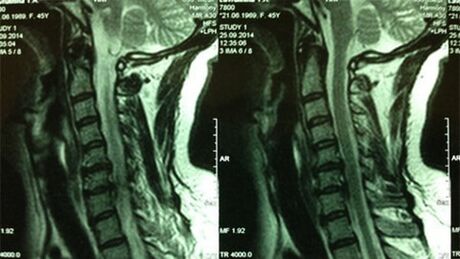

- X -raggi del dipartimento cervicale; Nella fase iniziale del processo, la risonanza magnetica del dipartimento cervicale sarà più istruttiva - garantirà una visualizzazione di alta qualità dei tessuti solidi e molli - mostrerà la condizione dei dischi intervertebrali, la presenza di osteofiti, le deformazioni, il danno alle radici nerve e i vasi sanguigni; valuterà la condizione dei legamenti, dei muscoli, del tessuto osseo;